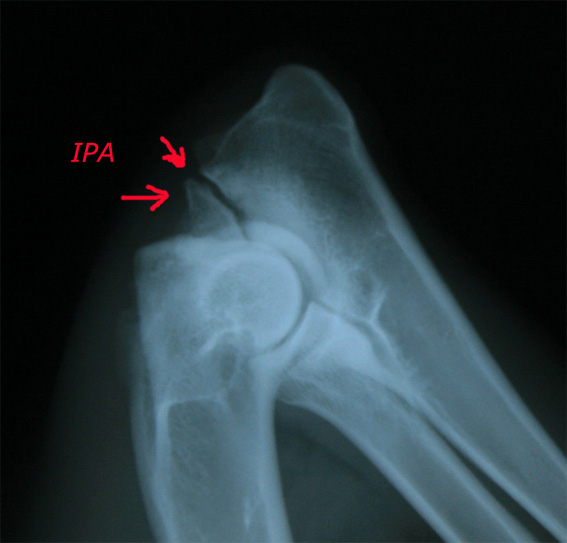

3. IPA (Isolierter Processus anconaeus) Beim Processus anconaeus (PA) handelt es sich um einen Knochenvorsprung der Elle, dessen Wachstumsfuge im Alter von 16 bis 20 Wochen geschlossen sein sollte. Fehlt diese knöcherne Verbindung, liegt ein Krankheitsbild vor, das folgende Ursachen haben kann: Ein verzögertes Längenwachstum der Elle, dadurch Druckveränderung und Irritationen, führt in seiner Wachstumsfuge zu Störungen der Verknöcherung und zum Isolierten PA. Bei einer zu engen Gelenkpfanne (Incisura trochlearis) der Elle entsteht Druck auf den PA und dem medialen Kronfortsatz. IPA tritt häufig bei Deutschen Schäferhunden auf. Bis zum Alter von sieben Monaten kann versucht werden den PA mit einer Schraube zu fixieren. Danach ist eine Entnahme angezeigt.

Röntgenbild DSH, 12 Monate, linkes Ellbogengelenk, seitlicher Strahlengang, gebeugtes Gelenk. IPA. Nicht dislozierter isolierter Processus anconaeus . Eine Stufenbildung zwischen Radius und Ulna ist nicht erkennbar.